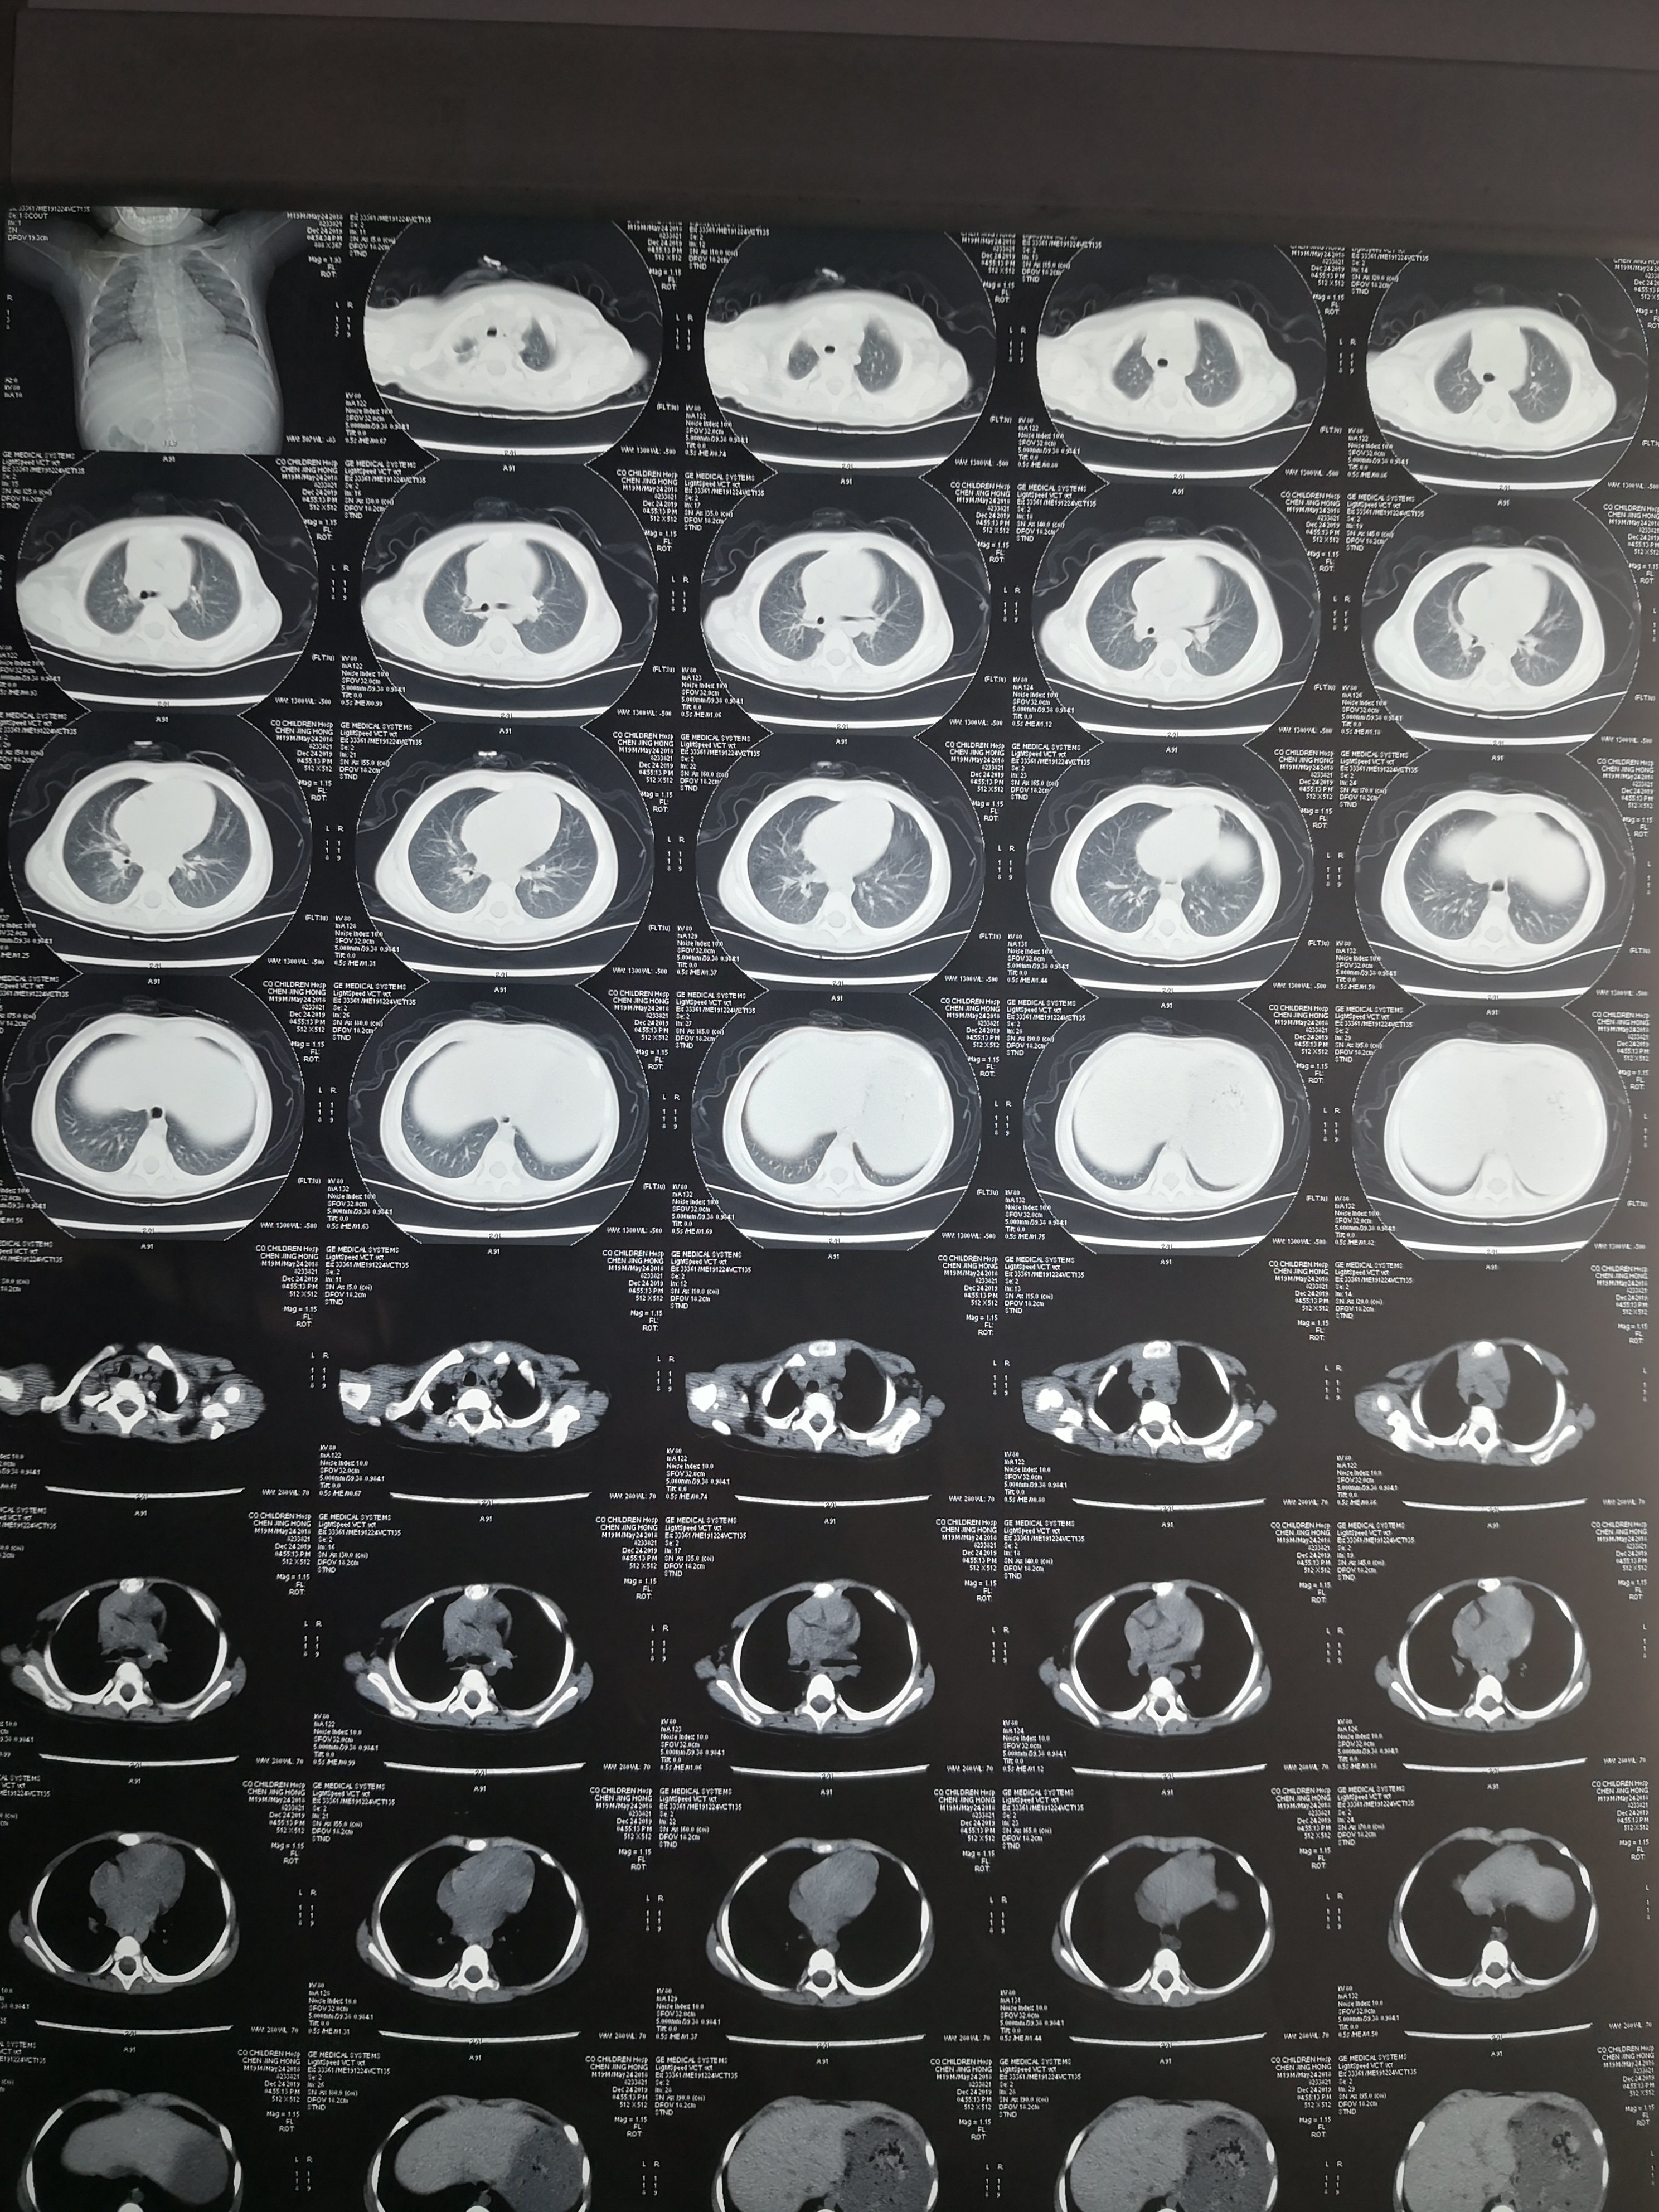

双肺炎症非常明显。CT结果出来后立即予以支气管镜灌洗治疗,在灌洗治疗过程中发现小朋友气管支气管里面大量黑色粪渣伴有较多黄色粪汁,遂将每个肺叶肺段灌洗干净,一周内完成2次支气管镜的灌洗治疗。第二次灌洗的时候双肺已经比较干净。出院后又口服了两周的强力抗生素。两周后复查胸部CT,结果如下

经过积极的救治,该小朋友双肺基本完全恢复正常。值得庆幸的是未留下任何肺部及大脑等重要脏器的后遗症。在这个小朋友的治疗过程中非常重要的治疗措施就是积极的予以支气管镜的灌洗治疗,及时清除了肺及气管支气管内的粪渣及粪汁,才能使得小朋友顺利康复!